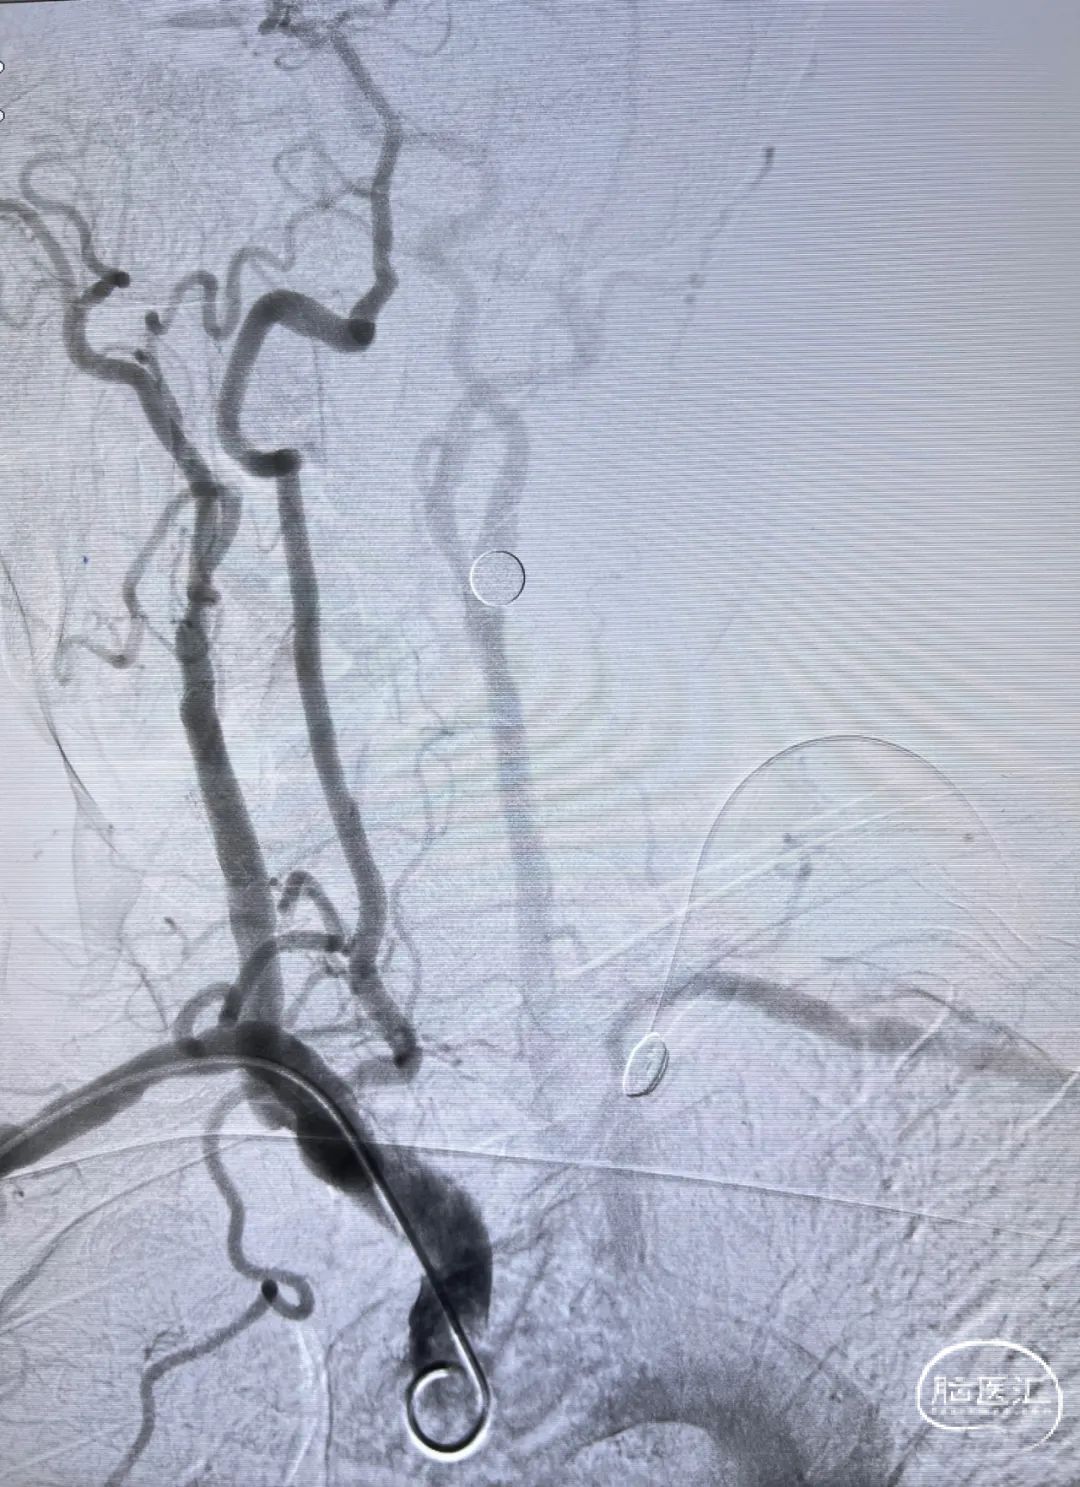

通路建立:经右侧桡动脉近桡穿刺,在赛诺APEX TRA GC™ SIM2-130cm内管的指引下将赛诺APEX TRA™ 6F 95cm经桡远端通路导引导管送行到颈总动脉末端。

5mm保护伞顺利到位,系统稳定。

5×30mm 扩张球囊到位,球囊扩张过程系统稳定。

通路弓上系统稳定支撑, 8×40mm Precise自膨支架顺滑到位。

支架系统释放过程,系统稳定。

左侧颈内动脉正侧位造影,狭窄解除。